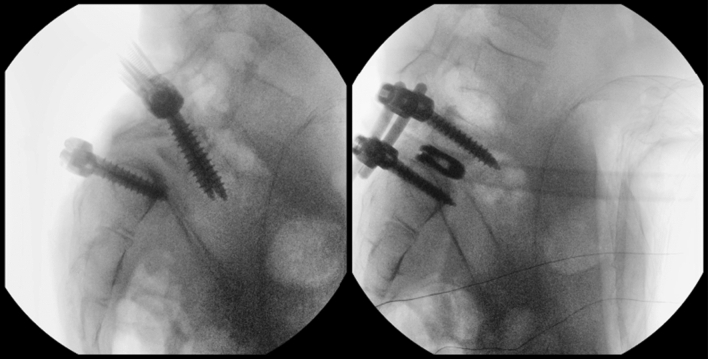

Then, two lordotic rods were simultaneously engaged in the S1 screws and two persuaders were placed on the L5 reduction screws and progressively tightened, while the reamers-distractors acted as levers to facilitate reduction. The manoeuvre was performed gradually, always paying attention to the L5 roots. Finally, two titanium cages were placed, and compression was performed to restore L5-S1 lordosis (Fig. 7).

Fig. 7.

Final reduction is checked by fluoroscope